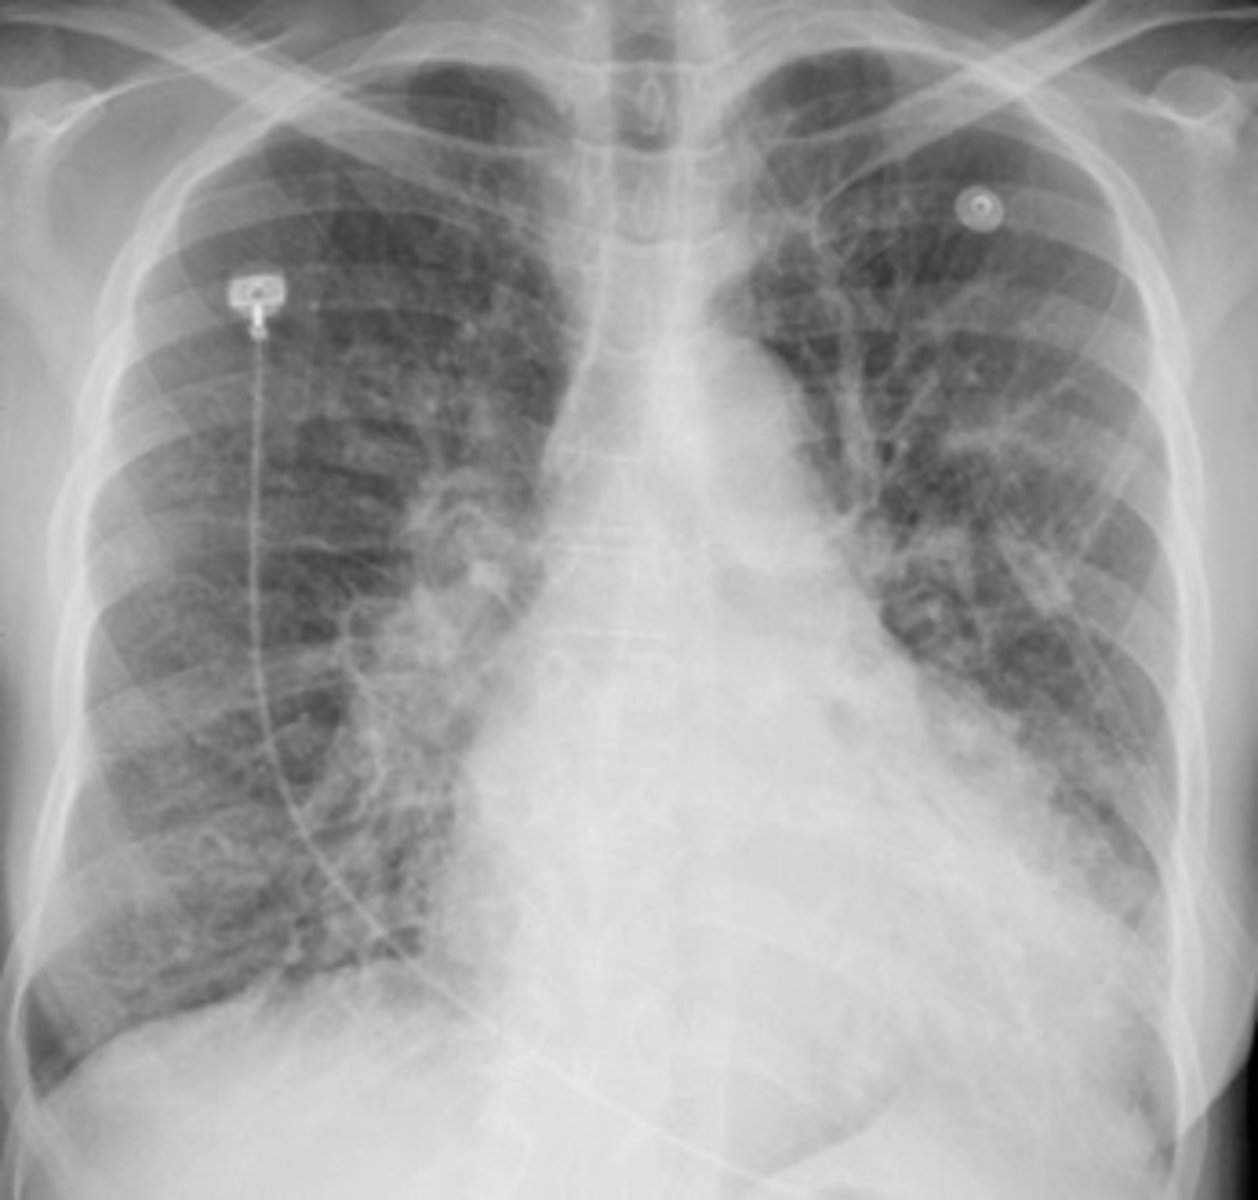

ARDS